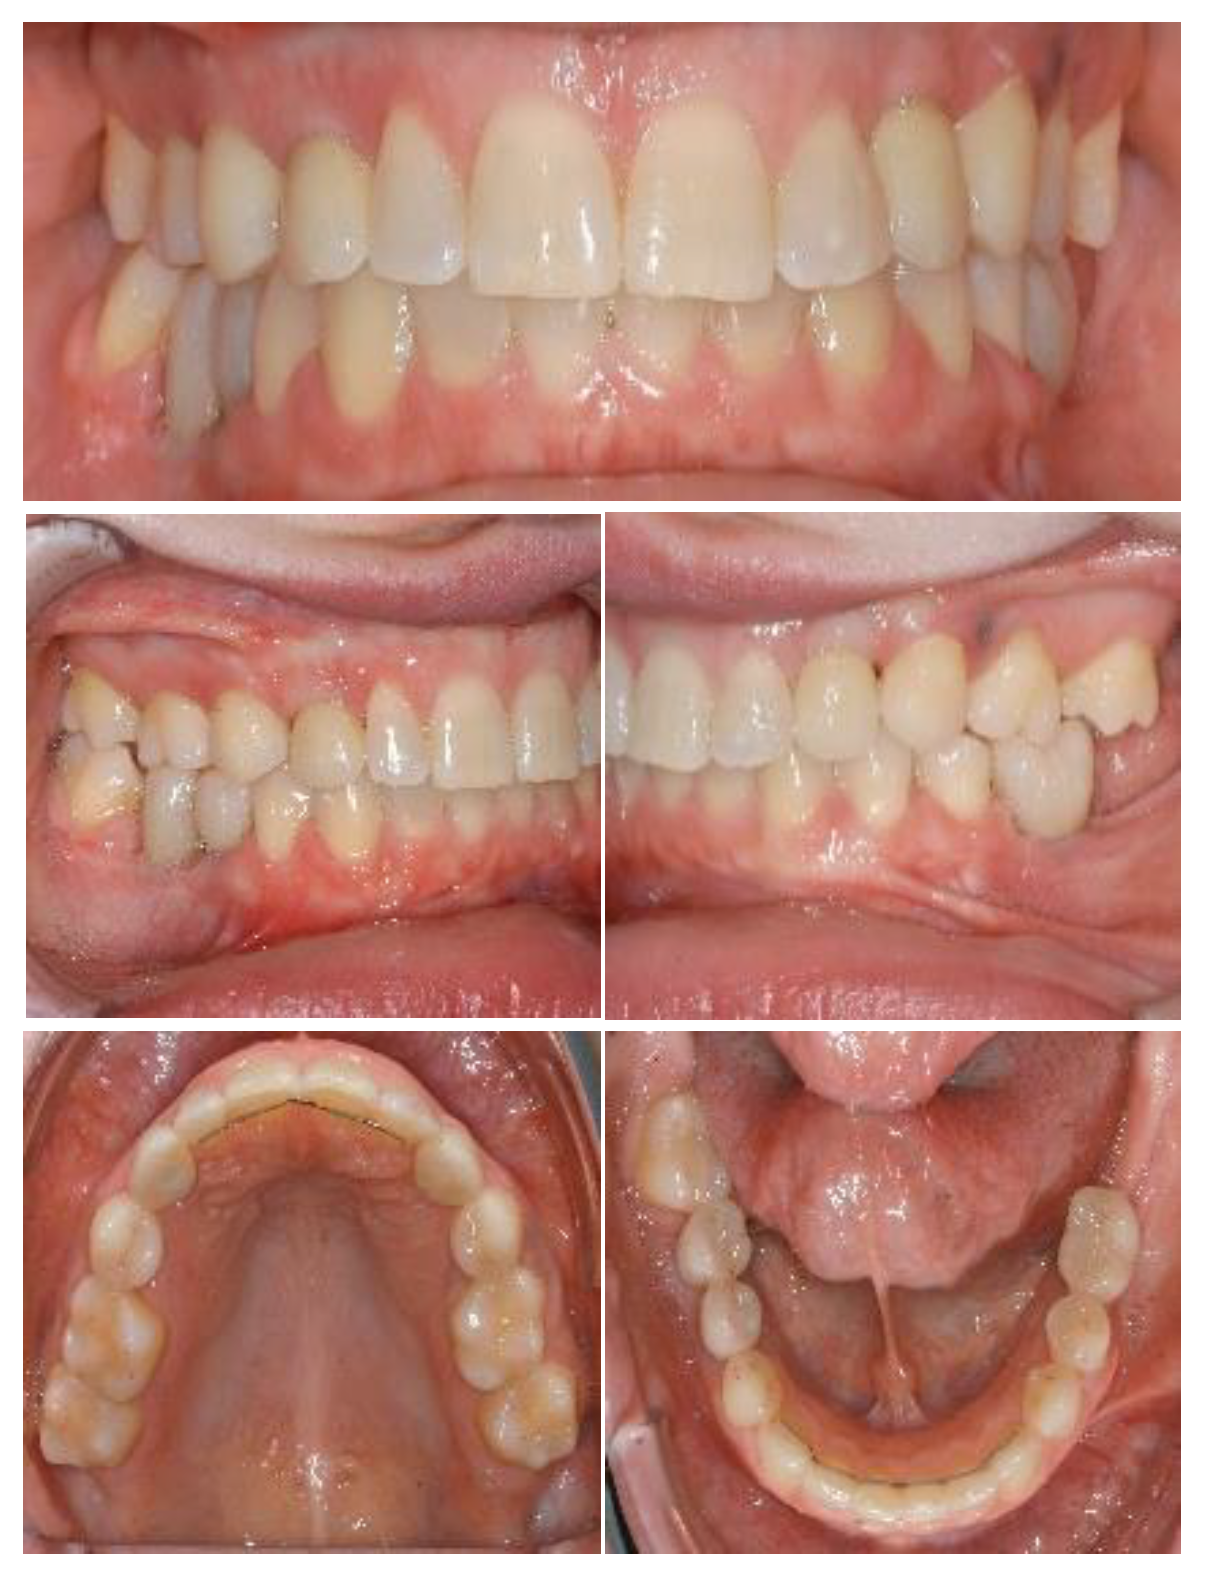

Figure 6.

Intraoral situation after orthodontic treatment and extraction of deciduous teeth.

Figure 7.

Initial panoramic radiography.